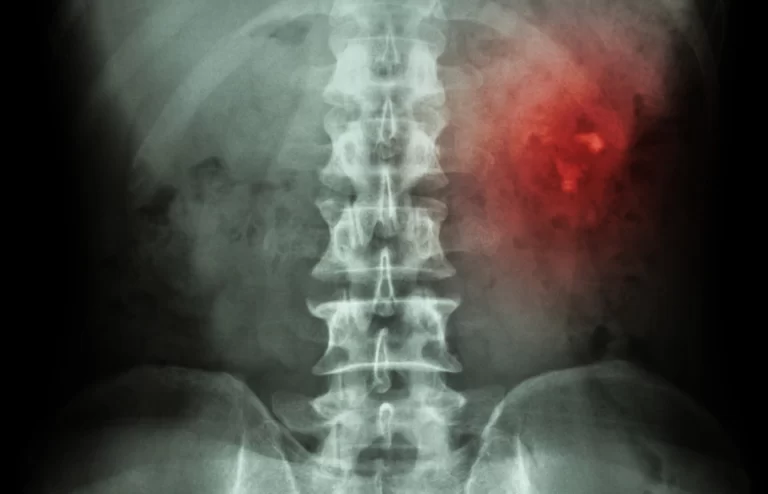

A confirmação do diagnóstico dos cálculos renais é realizada, na maioria dos casos, por Ultrassom ou Tomografia Computadorizada que pode estar relacionada ao quadro clínico de uma cólica renal ou em achado de em exames de imagens para outras hipóteses diagnósticas. Pode-se também somar o diagnóstico exames de sangue, urina e até mesmo análise do cálculo urinário. Depois do diagnóstico de cálculo renal, procura-se identificar as suas gênese, como: histórico médico pessoal, antecedentes familiares, hábitos alimentares e esportivos, tipo e quantidade de ingesta hídrica e estudo da anatomia urológica. Soma-se a anamnese, exames de sangue e urina que visam avaliar fatores metabólicos que podem levar a formação do cálculo urinário.